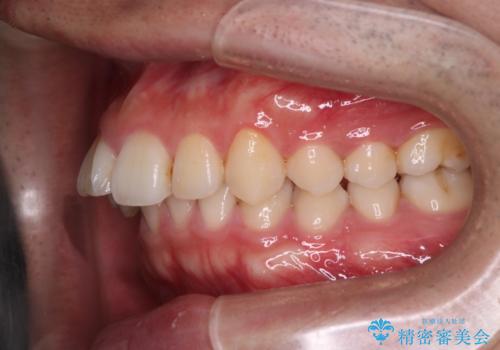

- 前歯が出ていることを主訴に来院されました。

歯列の幅が狭かったため、横に広げながらスペースを作り、叢生の改善を行いました。

左側の犬歯関係も治療前より良い状態で治療を完了することができました。

今回は臼歯部の遠心移動を行うために2級ゴムを使用しています。